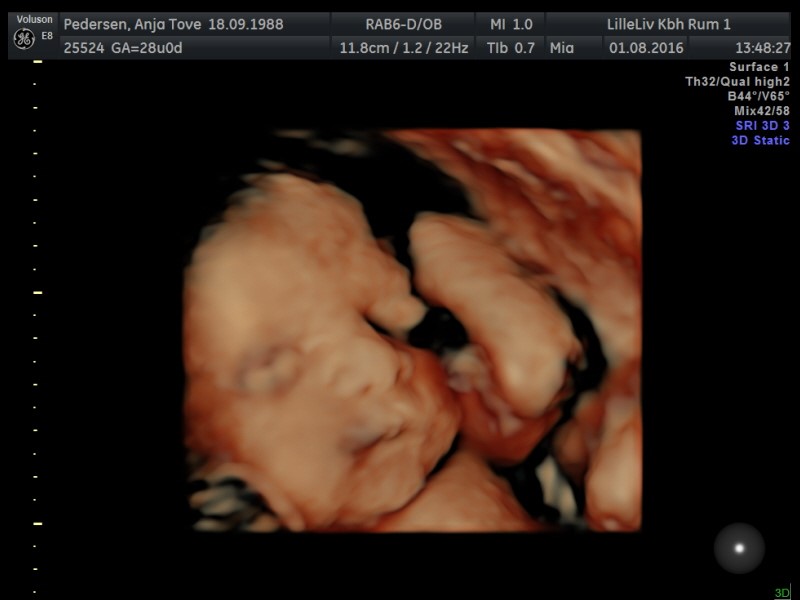

Vi har valgt gaver fra til hinanden og i stedet tog vi til 3D/4D skanning for at se til prinsessen

Hvilken fantastisk oplevelse! Hun startede med at have foden i hovedet, men hun var dog lidt sød og lagde sig anerledes så vi kunne se hendes smukke ansigt

Og nej hvor hun ligner sin far! Og dermed ligner hun altså også Isaac virkelig meget, ingen tvivl om hvem hverken far eller storebror er!

Billeder af maven bliver ikke denne gang, men af prinsessen i 3D

Vedhæftede fotos (klik for at se i fuld størrelse)